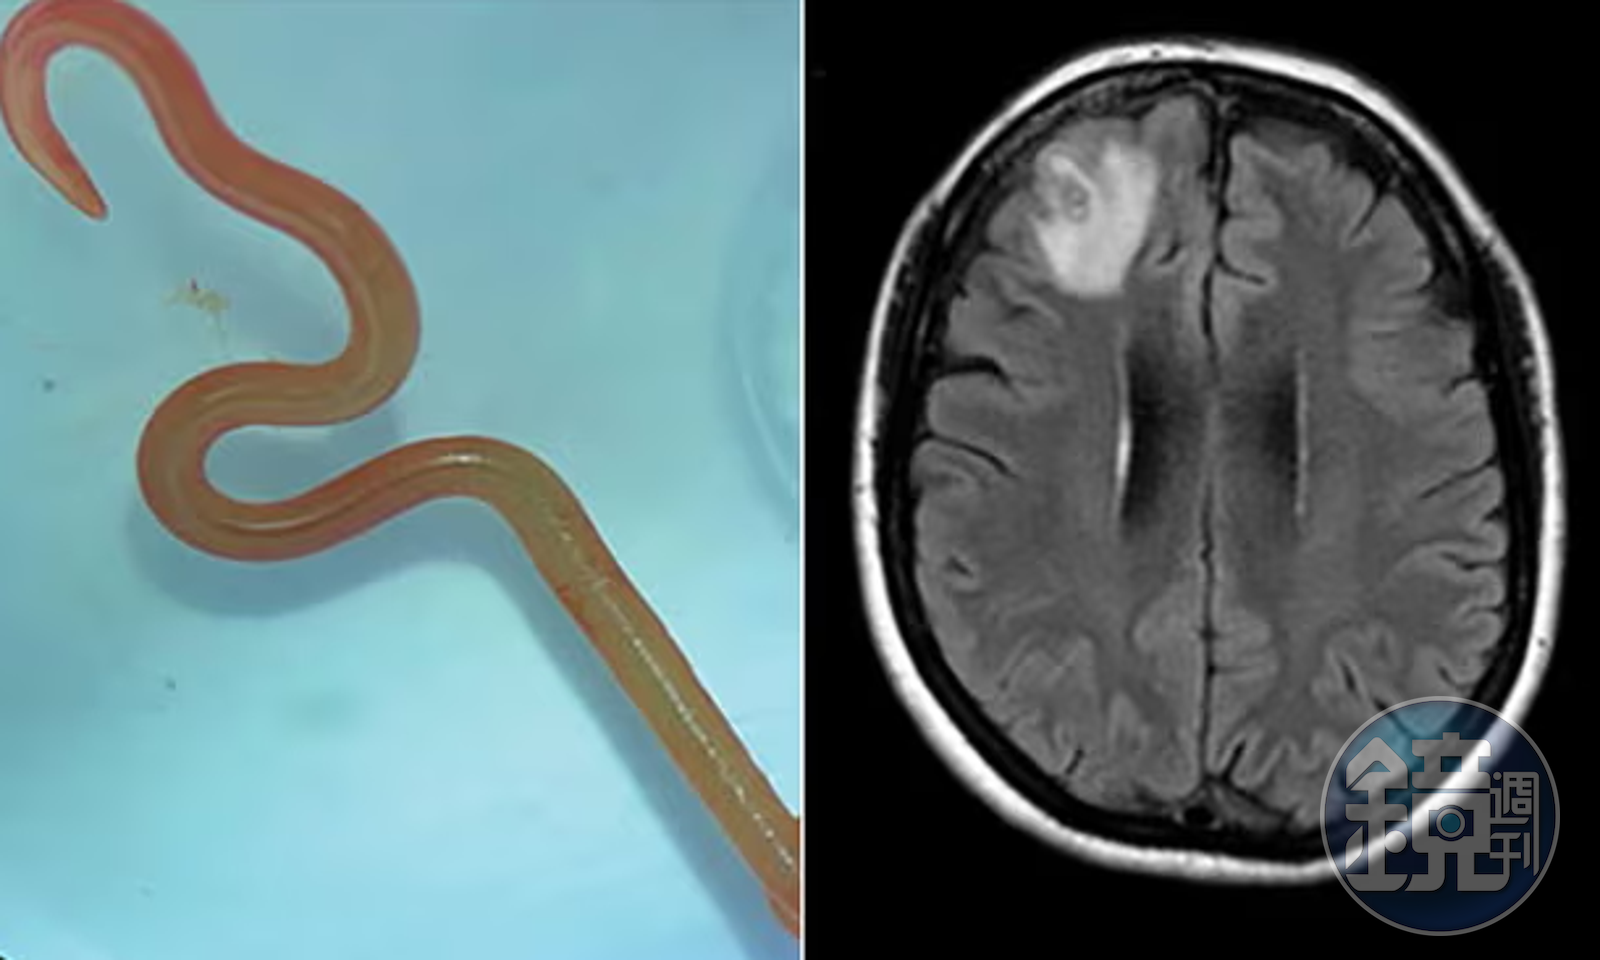

報導指出,這條8公分活體蛔蟲寄生在婦人的大腦裡,之後醫師從婦人受損的腦額葉中取出這條蟲蟲,而且蟲蟲被取出時還是活跳跳狀態,醫師也研判,蟲蟲寄生在婦女腦內已達2個月。傳染病科醫師賽納納亞克(Sanjaya Senanayake)就形容:「當醫師用鑷子夾起這個物體時,手術室裡的每個人都震驚無比,因為發現這是一條蠕動的、活的8公分紅色蠕蟲。」

據悉寄生在婦人腦內的蛔蟲名叫「Ophidascaris robertsi」,這種蛔蟲通常寄生在澳洲常見的地毯蟒蛇體內。澳洲寄生蟲專家侯賽因(Mehrab Hossain)在《新發傳染病》(Emerging Infectious Diseases)期刊上就指出,他懷疑這名婦人可能吃下被蟒蛇糞便和寄生蟲卵汙染的植物,之後成為「意外宿主」。